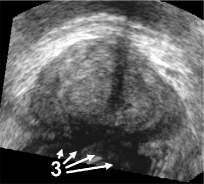

The framework was validated on 278 registrations of 295 US volumes from 17 patients. The 17 reference images were acquired shortly before the intervention, and the tracking images were acquired after a biopsy shot. The clinical protocol was approved by the ethical committee of the XXX hospital, Town, Country, and all patients consented to participate to the study. The images were acquired with a GE Voluson and a RIC5-9 endorectal US probe. The algorithms were executed on a 4-core 2.6Ghz processor. In order to provide a reference gold standard for the evaluation of registration accuracy, experts manually segmented 467 point fiducials that were clearly identifiable on multiple images (e.g. calcifications and cysts). The distances between fiducial pairs were measured after registration to estimate the local accuracy. Note that the unavoidable segmentation error increases the measured error in average; this approach hence underestimates accuracy. Accuracy was computed for all registrations that were qualified as valid by experts after visual inspection, which represent 97,8 of the registrations. The results for both rigid and elastic registration are given in Tab. 1, and a visual illustration of the registration performance is given in Fig. 2. Fig. 3 shows 3D biopsy maps created with our biopsy tracking system.